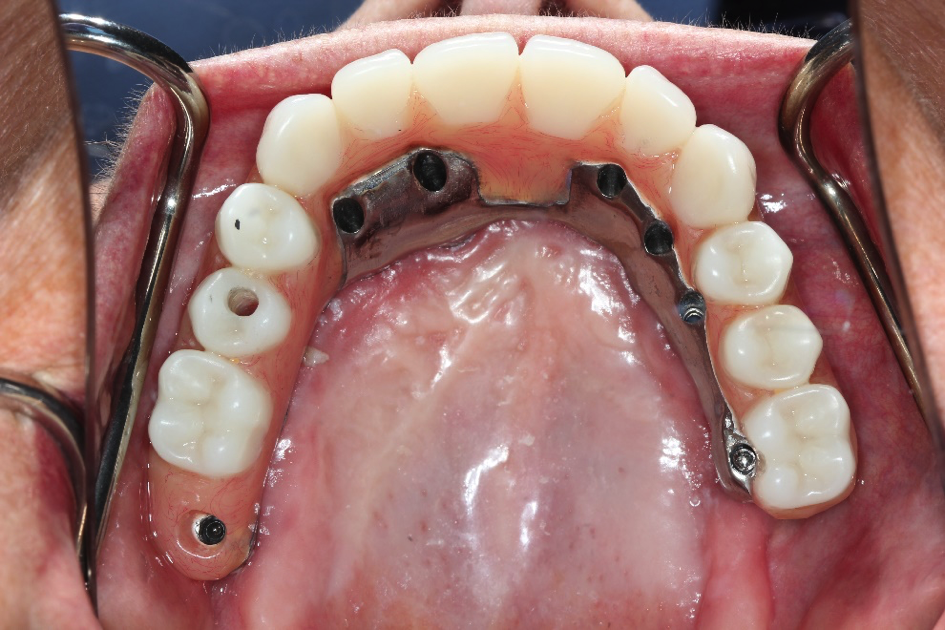

This patient came to us with a broken denture and bar. She wanted teeth that would make her smile again. We fabricated her a new bar that attached to her implants and placed teeth on them. This is a permanent bridge that is made of titanium and acrylic.